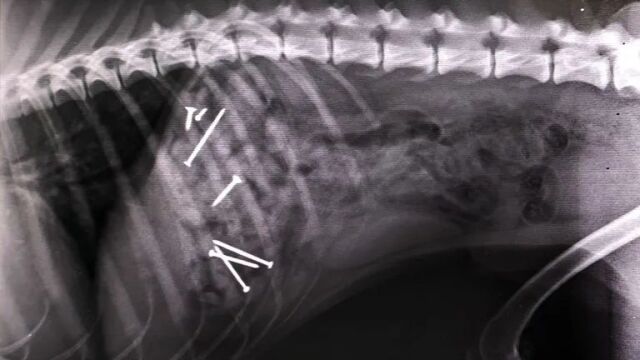

Perro al que intervinieron hace dos años por comer salchichas con clavos en VigoAntena 3 Noticias

En la primera de las ubicaciones se han encontrado salchichas con clavos en su interior. Las esconden entre las hojas y el olor atrae a los perros. Cuando el animal ingiere la comida, es básico llevarlo a un veterinario para que pueda operar al can y evitar, así, la muerte. Pero no es el único cebo que se ha encontrado en los últimos días. En el Arenal la trampa va más allá.